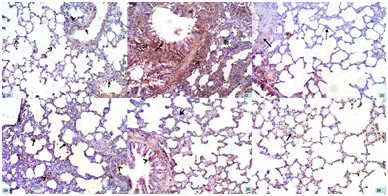

Lung

NF-κBimmuno-stained sections of control lung specimens demonstrated mild positive cytoplasmic immunoexpression in the epithelial cells lining the expanded alveoli, bronchioles, as well as in the cells of connective tissue septa (Figure 21). The lungs of the AP group were characterized by the presence of intense cytoplasmic immunoreactivity in the epithelial cells lining the alveoli, bronchioles, as well as cells present within the thickened interalveolar septa (Figure 22).

Regarding lung sections of bee venom pretreated rats (BVL group), they showed areas with moderate cytoplasmic immunoreaction in the epithelial cells lining the alveoli, bronchioles, blood vessels, as well as cells present within interalveolar septa. Other areas showed negative immunoreaction (Figure 23). Both bee propolis pretreated rats (BPL group) and combined therapy treated rats (CT group) showed moderate cytoplasmic immunoreaction in the epithelial cells lining the alveoli, bronchioles, as well as cells present within the thickened interalveolar septa (Figures 24&25).

In bee venom only treated rats (BV group), they showed mild positive cytoplasmic immunoexpression in the epithelial cells lining the expanded alveoli, as well as in the cells of connective tissue septa (Figure 26). No remarkable difference was observed in bee propolis only treated rats (BP group) compared with group VI.

Figure 21 A photomicrograph of a section of a rat lung in group I (CG) showing mild positive cytoplasmic immunoexpression in the epithelial cells lining the expanded alveoli (dotted arrows), bronchioles (arrows), as well as in the cells of connective tissue septa (arrow head). NF-κB; x 200

Figure 22 A photomicrograph of a section of a rat lung in group II (AP group) showing intense cytoplasmic immunoreactivity in the epithelial cells lining the alveoli, bronchioles (arrow), as well as cells present within the thickened interalveolar septa (dotted arrows). NF-κB; x 200

Figure 23 A photomicrograph of a section of a rat lung in group III (BVL group) showing areas with moderate cytoplasmic immunoreaction in the epithelial cells lining the alveoli (thin arrow), bronchioles, blood vessels (thick arrow), as well as cells present within interalveolar septa. Other areas show negative immunoreaction (dotted arrow). NF-κB; x 200

Figure 24 A photomicrograph of a section of a rat lung in group IV (BPL group) showing moderate cytoplasmic immunoreaction in the epithelial cells lining the alveoli (arrows), bronchioles (arrow head), as well as cells present within the thickened interalveolar septa (dotted arrow). NF-κB; x 200

Figure 25 A photomicrograph of a section of a rat lung in group V (CT group) showing moderate cytoplasmic immunoreaction in the epithelial cells lining the alveoli (thin arrow), bronchioles (arrow head), as well as cells present within the thickened interalveolar septa (thick arrow). NF-κB; x 200

Figure 26 A photomicrograph of a section of a rat lung in groups VI (BV group) showing mild positive cytoplasmic immunoexpression in the epithelial cells lining the expanded alveoli (thin arrow), as well as in the cells of connective tissue septa (thick arrow). NF-κB; x 200